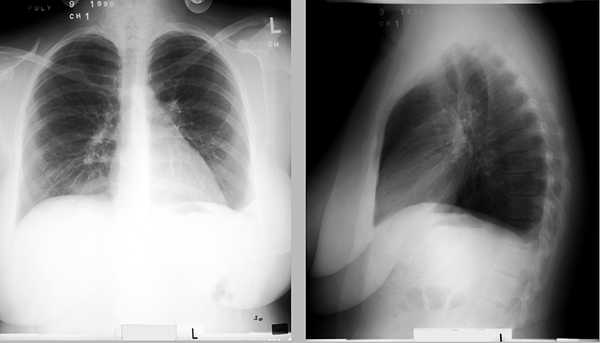

El paciente es un 20 año - viejo estudiante hembra de colegio con una seis historia de año de fumar. Ella actualmente usa pastillas anticonceptiva. Ella tuvo un un mes de historia del dolor derecho de flanco y dorso, que se trató con la tracción a su hospital local. al tiempo de entrada a su hospital local había un lado derecho infiltra con un derecho pequeño pleural efusión. UN V/Q repasa se leyó tan la probabilidad bajo. El paciente se despidió sobre nonsteroidal anti - inflamatorias drogas. El paciente se admitió a la Universidad de Iowa un mes luego, después de ser ver en la clínica de paciente de consulta exterior para síntomas recurrentes de dolor posterior.

La sala ventila el gas arterial de sangre mostró pH 7.41, PCO2 35 y PO2 91. El EKG era normal, y la radiografía de pecho ningún mostró infiltra pero embotando al izquierda costophrenic ángulo. El lado derecho, donde la frotación se oyó, era normal. La extremidad más inferior dopplers se obtuvieron y eran normales. Una ventilación perfusion repasa se obtuvo e interpretada tan la probabilidad intermedia para la embolia pulmonar.

A causa del interés continuado sobre la embolia pulmonar, pulmonar angiography se desempeñó y demostrado un cuadrilongo que llena falla dentro de la interlobar sucursal de la arteria pulmonar derecho. Esta falla extendió en el lóbulo medio así como también un proximal segmento del lóbulo más inferior derecho.